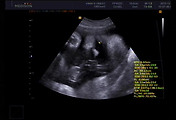

예정일은 1월 26일에 변함은 없습니다.

몸무게가 2.4kg으로 같은 시기의 후니가 2.9kg이었으니 후니 보다 조금 작습니다.

대신 양수는 정상 범위에서 많아 배는 많이 불러보이구요..

그 외 특이사항은 없군요.